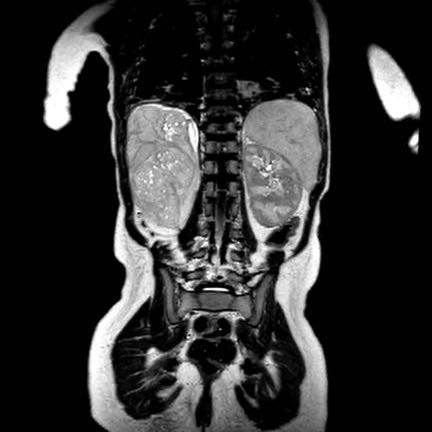

Trên MRI, nephroblastomatosis được quan sát rõ nhất trên các chuỗi xung sau tiêm thuốc tương phản từ và chuỗi xung khuếch tán (DWI).

Hình ảnh

Các hình ảnh MRI của cùng bệnh nhân cho thấy tình trạng giảm tưới máu của mô bệnh lý và hạn chế khuếch tán mạnh với giá trị ADC thấp.

Bệnh nhân được điều trị hóa trị liệu tiền phẫu, sau đó khối u ở bên trái được cắt bỏ qua phẫu thuật cắt thận bán phần. Nephroblastomatosis lan tỏa được điều trị bằng phác đồ hóa trị AV (Actinomycin D và Vincristin) hàng tháng trong một năm.